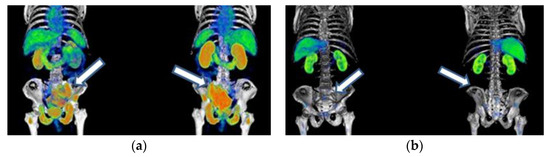

Figure A2. Patient with mCRPC who had a complete response to 177Lu-iPSMA treatment: (a) anterior and posterior 68Ga-iPSMA imaging before 177Lu-iPSMA treatment, and (b) after 177Lu-iPSMA therapy (three doses of 7.4 GBq). Arrows indicate tumor lesion sites.

177Lu-iPSMA showed an overall response rate of 36.6% (Table 2). Figure 2 and Figure 3 show typical clinical cases of complete response (disappearance of all lesions or adenopathies less than 10 mm short axis) and partial response (decrease of at least 30% in the sum of the largest diameters of lesions compared with the baseline study) after 177Lu-iPSMA therapy. In addition, the reduction of large tumors and multiple metastatic lesions are proof of the high specificity and molecular recognition of 177Lu iPSMA by PSMA at the tumor cell level (Appendix A) (Figure A1, Figure A2 and Figure A3).

177Lu-iPSMA therapy is a convenient option for the treatment of multiple metastases and large tumor lesions (Appendix A) (Figure A1, Figure A2 and Figure A3). For example, in the case shown in Figure A1, the patient suffered from severe pain characteristic of the terminal stage of the disease. However, two weeks after administration of the first dose of 177Lu-iPSMA, the subject showed relevant pain relief. Furthermore, after administering four doses of 177Lu-iPSMA (four doses of 7.4 GBq), metastatic lesions in the hip and spine were significantly reduced, prolonging the patient’s life for 19 months after therapy. In this context and based on the results of this study, 177Lu-iPSMA therapy should be considered and evaluated in future clinical trials as a second-line rather than third- or fourth-line therapy in patients with mCRPC, with the potential to improve patient survival.